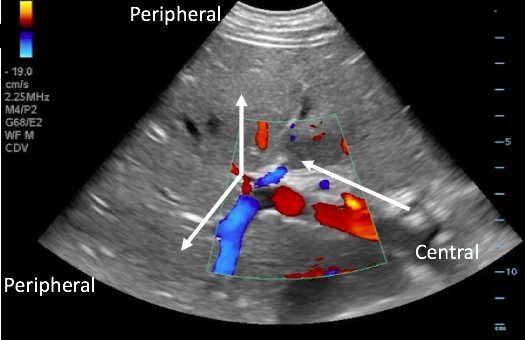

- Physiologic blood flow in the portal vein is from deep (the spleen and intestines) to superficial (the liver periphery), towards the probe.

- With the probe on the anterior abdominal wall, blood in the portal vein flows from central (the mesenteric and splenic veins) towards the liver and will be red when color Doppler is applied. The middle and left portal venous branches will still appear red. However, blood in the right portal venous branch will flow deep into the right lobe, appearing blue.

Figure 17. Color Doppler image with arrows illustrating normal portal venous blood flow, from the center towards the periphery of the liver.

- May indicate portal hypertension, as increased pressure forces blood back towards the spleen and intestines

- Blue flow (away from probe) in the portal vein on color Doppler.